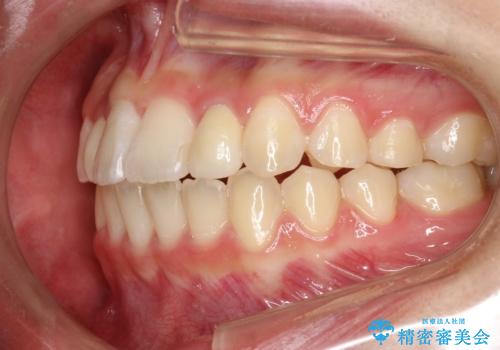

このような場合、矯正によりスペースを集め、本来あるべき形態にセラミックで修正することもできます。

時間はかかりましたが、きれいな笑顔になりました。

かぶせ物の種類:PFZ standard